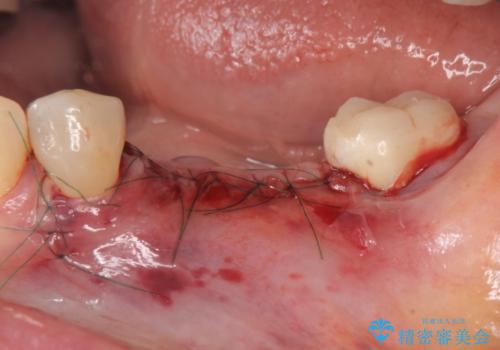

舌側にある大きな骨隆起を除去するとともに、除去した骨と人工骨を用いてインプラント周囲の骨を造成します。

自家骨と人工骨による骨造成は、長期的に見て安定し吸収が少ないとされる骨の造成法です。

インプラント周囲に、必要十分な骨を作ることが長期渡りインプラントにトラブルを起こしにくい鍵となります。